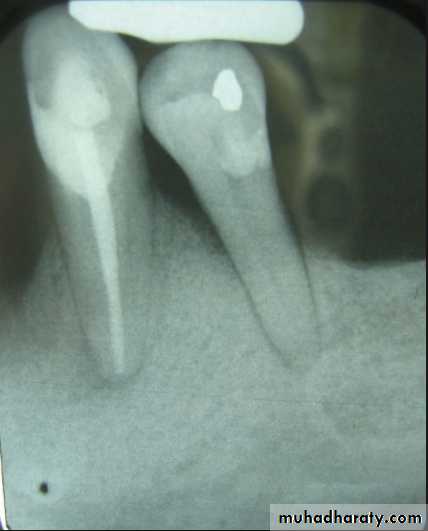

Evaluation of radiographic survey

All prospective abutment teeth must be critically evaluated4/2/2018

Root size, length and form

Teeth with large or long roots - Greater periodontal supportTapered or conical roots- un favorable

Multi rooted teeth with divergent roots are stronger abutment teeth than single rooted, multi rooted teeth with fused roots.4/2/2018

Signs of positive bone factor

A supportive trabecular patternHeavy cortical layer

Dense lamina dura

Normal bone height

Normal periodontal ligament space.

If retrograde bone changes occur, the patient has a negative bone factor ; prognosis is poor.